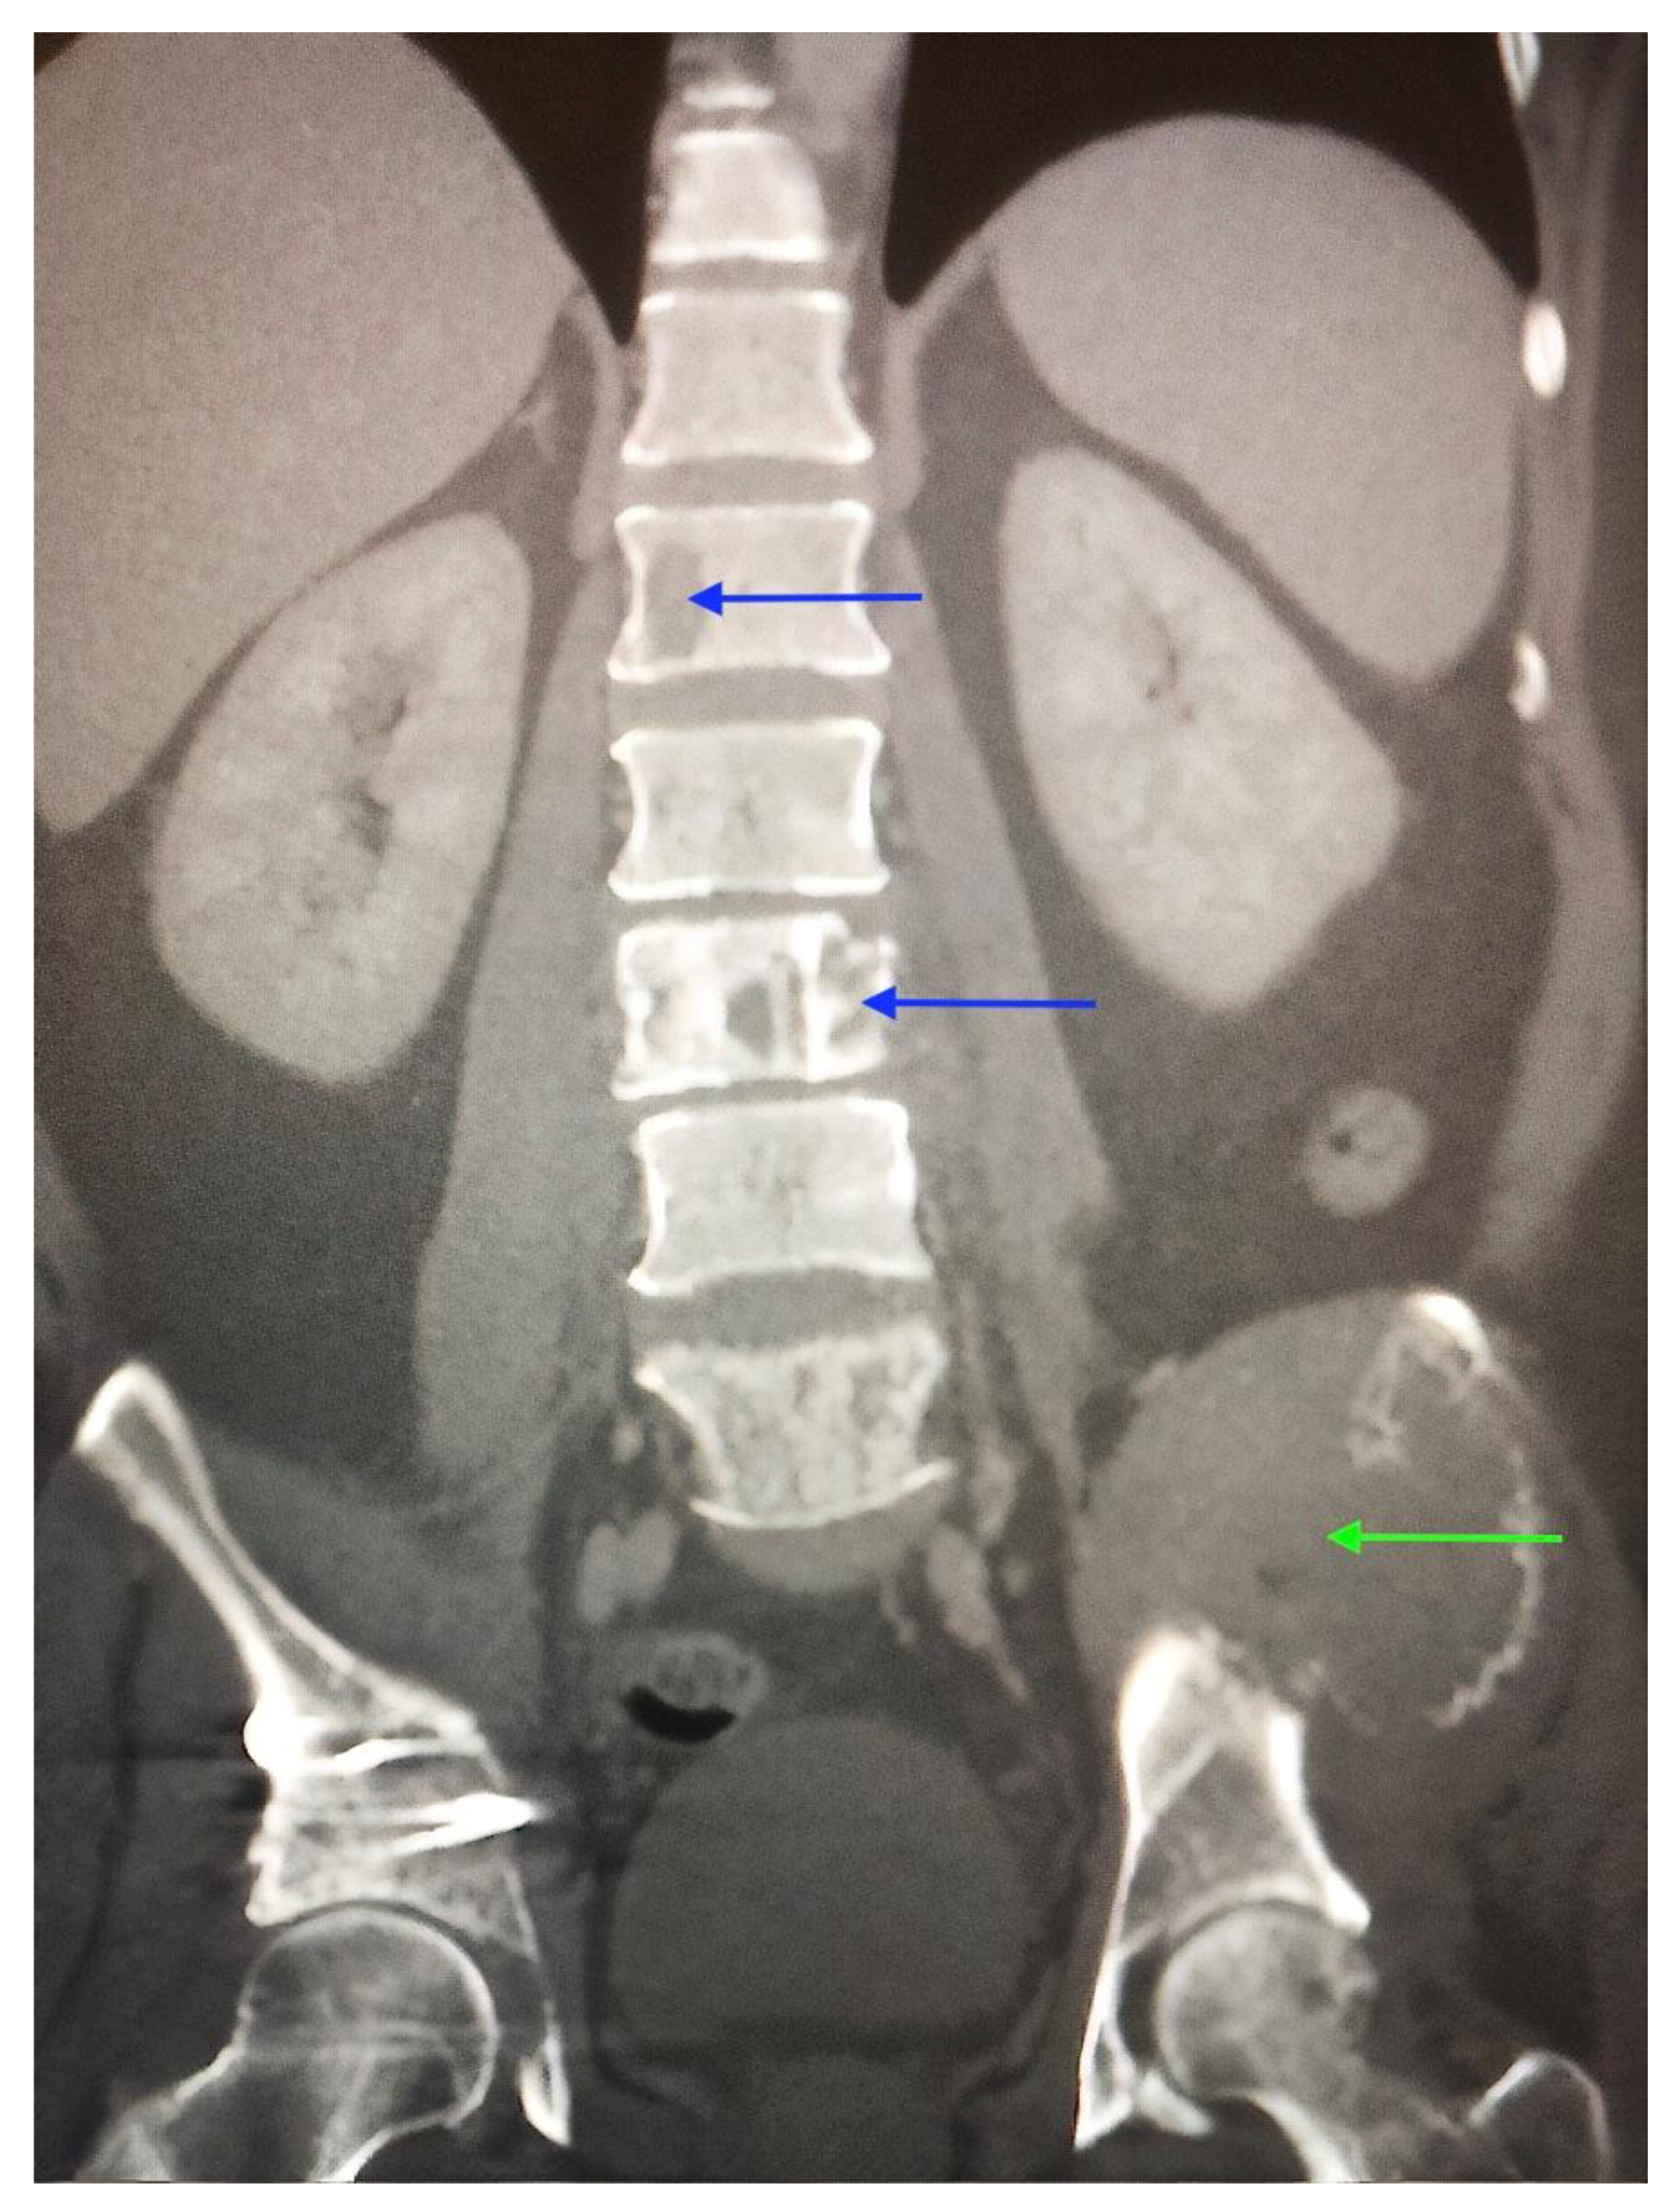

2. Case Report